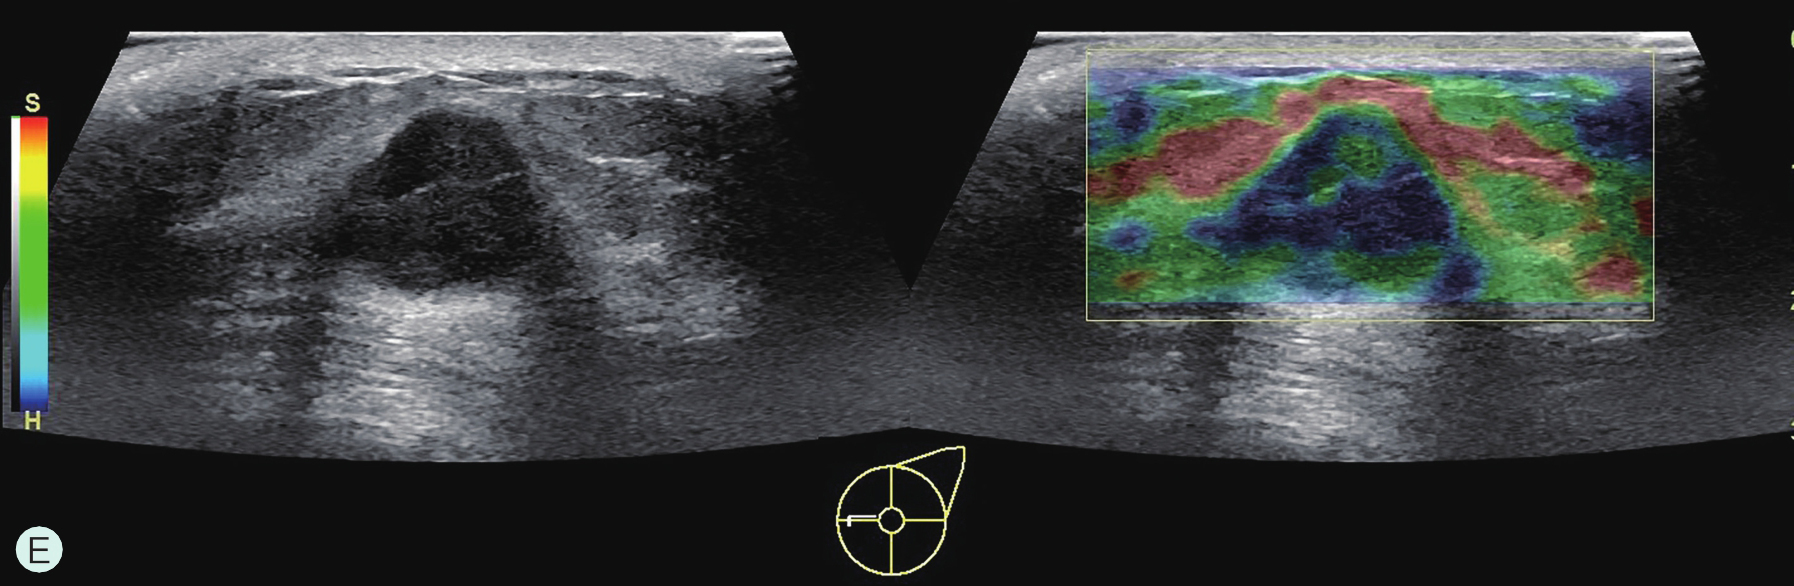

图2-2-1 确定造影病灶

A.病灶二维图像;B、C.病灶CDFI图像;D.同侧腋窝淋巴结情况;E.病灶弹性成像图像